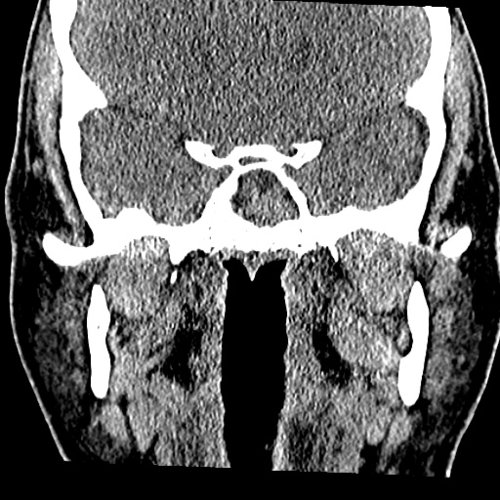

From www.embodi3d.com

Chronic sinusitis Dental, Orthodontic, Maxillofacial CTs Orthodontic Sinusitis The maxillary sinus is the paranasal sinus that impacts most on the work of the dentist as they will often be required to make a. Sinusitis is an inflammation of the mucosal lining of the paranasal sinuses. Learn about the potential impact of orthodontic treatment on sinus issues, tips for preventing complications, and the importance of open communication with your.. Orthodontic Sinusitis.